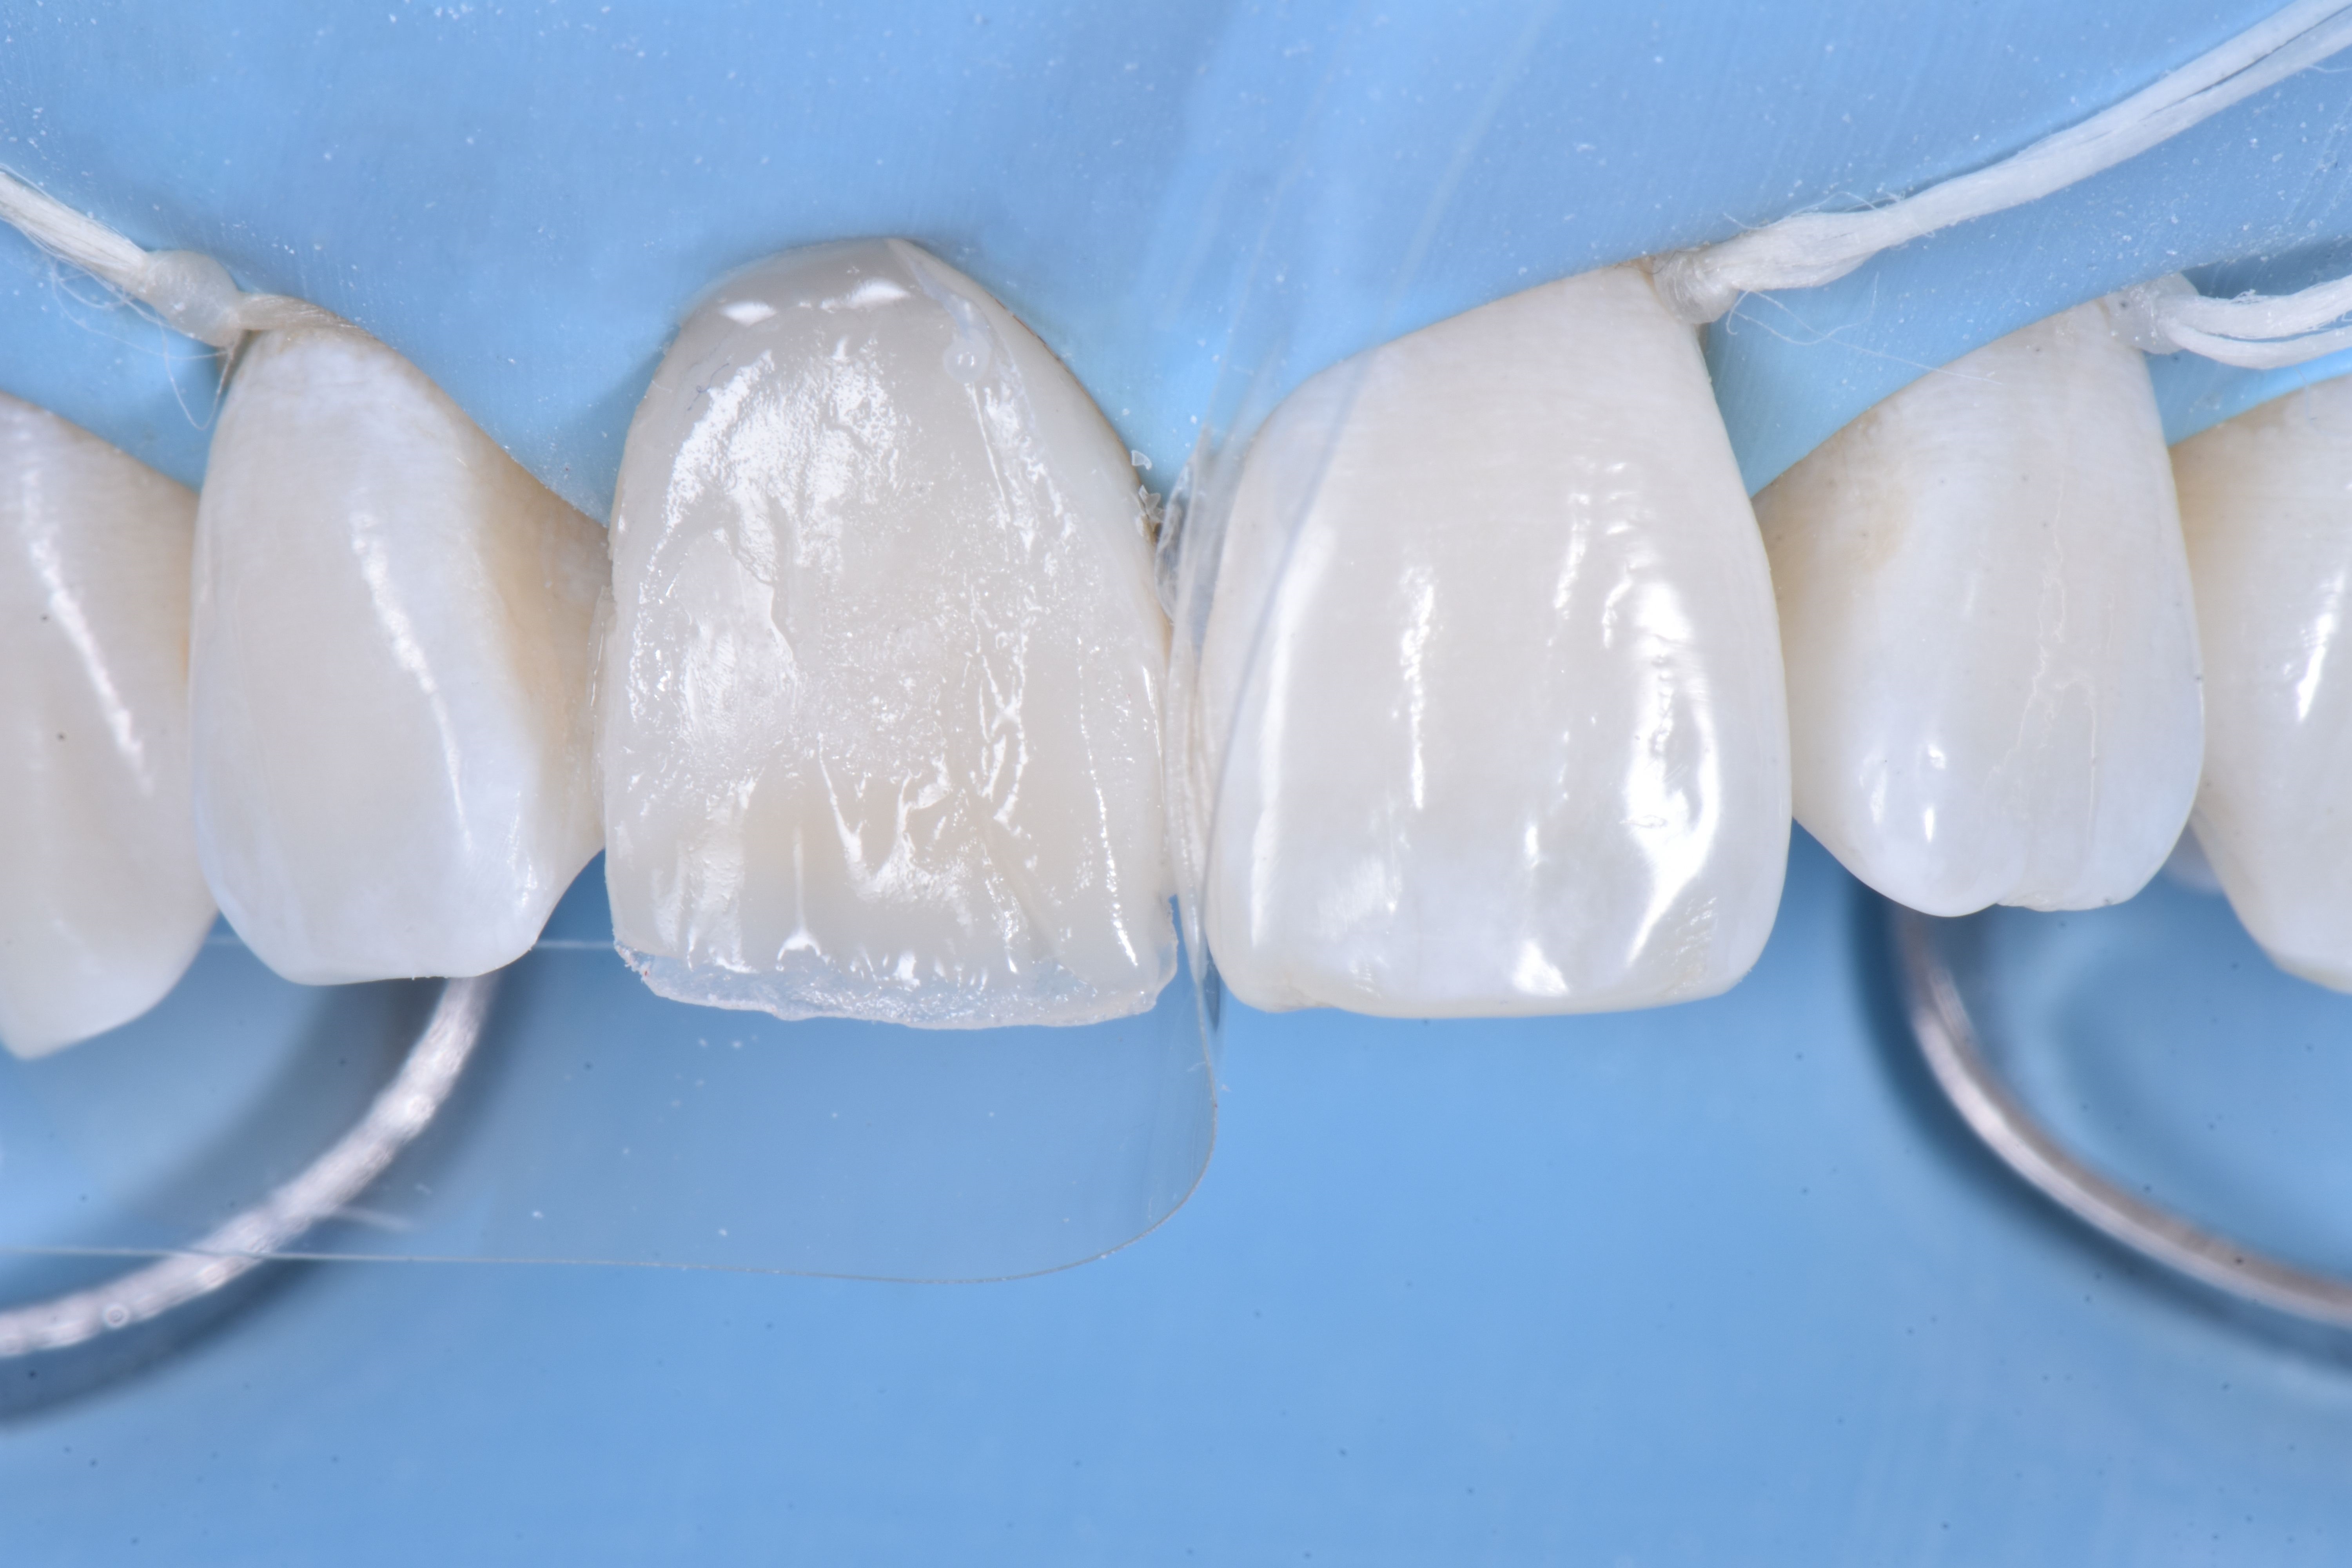

Z użyciem silikonowego indeksu diagnostycznego wykonanego na podstawie modelu wax-upu rekonstrukcję ściany od strony podniebiennej kompozytem w odcieniu szkliwa (ESTELITE ASTERIA WE firmy TOKUYAMA DENTAL) (ryc. 8).